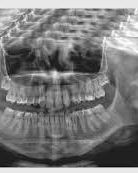

MyRay Hyperion X9 PRO

Panoramatický prístroj s RTG systémom 3 v 1

Hyperion X9 ponúka novú 3D technológiu, cefalometrické projekcie a širokú škálu 2D vyšetrení.

Hyperion X9 Pro spĺňa všetky diagnostické požiadavky pre ľahké začlenenie do pracovného režimu a zaručuje maximálny komfort pre pacienta a operátora. Snímky v kvalite SuperHD umožňujú lekárovi urobiť správnu diagnózu, plná dostupnosť a užívateľská intuitívnosť s inovatívnym plne dotykovým ovládacím panelom a virtuálnym panelom /PC interface/, vrátane „Face to Face“ systémom polohovania zaručujú maximum pohodlia pre pacienta a profesionalitu operátora. Široká škálovateľnosť a modularita Hyperion X9 Pro umožňuje zmeniť nastavenia podľa vašich aktuálnych potrieb.

2D PANORAMICKÉ VYŠETRENIA

- HD panoramatický röntgen a QuickPAN

- Kompletný a redukovaný panoramatický röntgen pre deti

- Ortogonálna projekcia pre celý chrup (znižuje prekrývanie zubných koruniek)

- Segmenty panoramatického röntgenu a chrupu s optimalizáciou vyhradenej projekcie

- Bitewing expozície v 4 segmentoch limitované na korunky, aby sa zvýraznili interproximálne dutiny